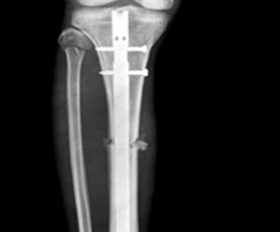

- 경골 간부 골절 > 금속판 : 12~18개월 / 골수정 : 18~24개월

- 금속판

- 골수정